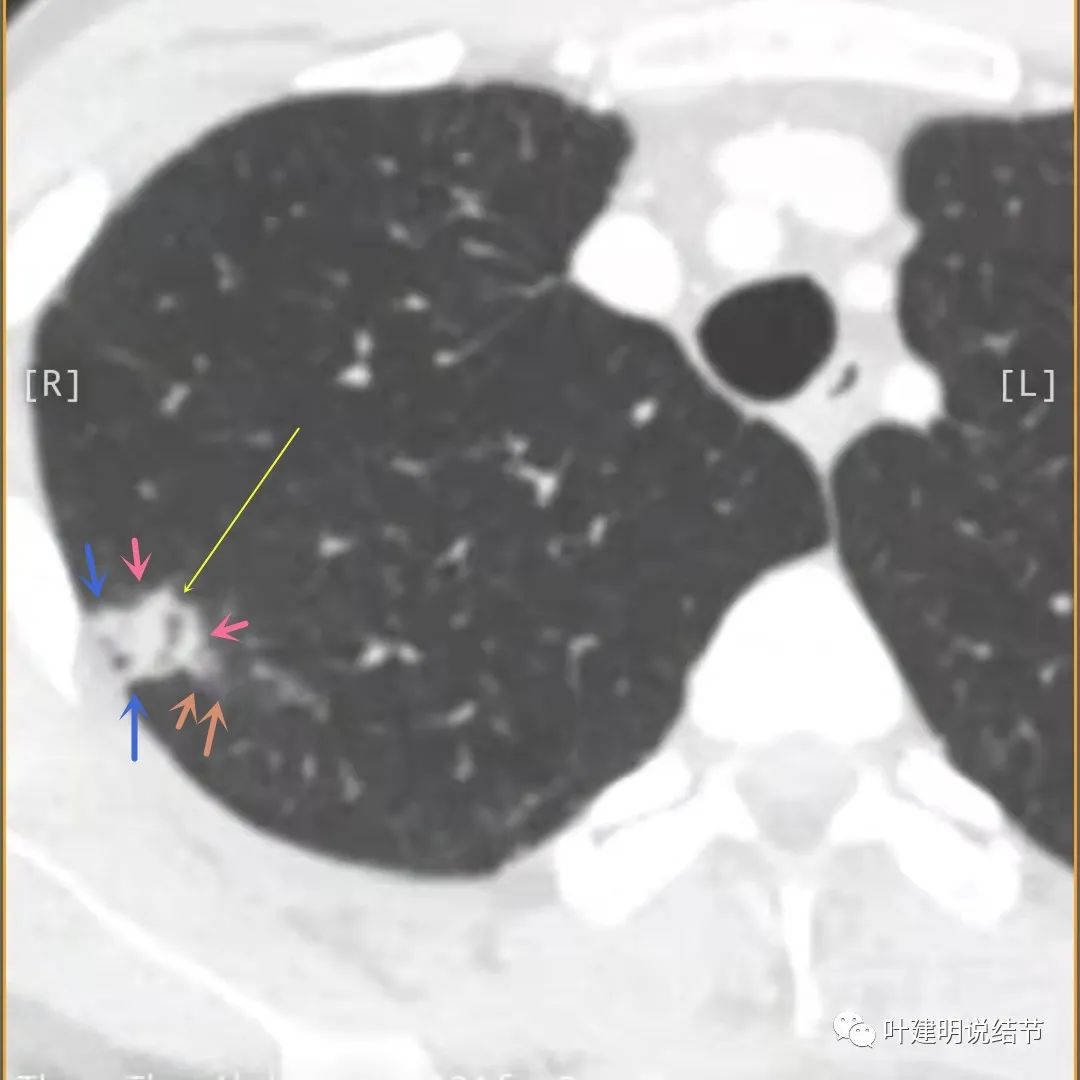

主病灶出现,粉色箭头示病灶密度较高,边上有磨玻璃影,甚淡(砖色箭头)

病灶有空洞(黄色箭头),主病灶边上见条索状高密度影(细红色箭头),邻近胸膜有粘连(蓝色箭头)

邻近胸膜明显增厚,且广基底,主病灶前方有小片磨玻璃影

主病灶与胸膜间基本相连,模糊清(蓝色箭头),主病灶壁厚薄欠均,边上有高密度条索状(桔色箭头)